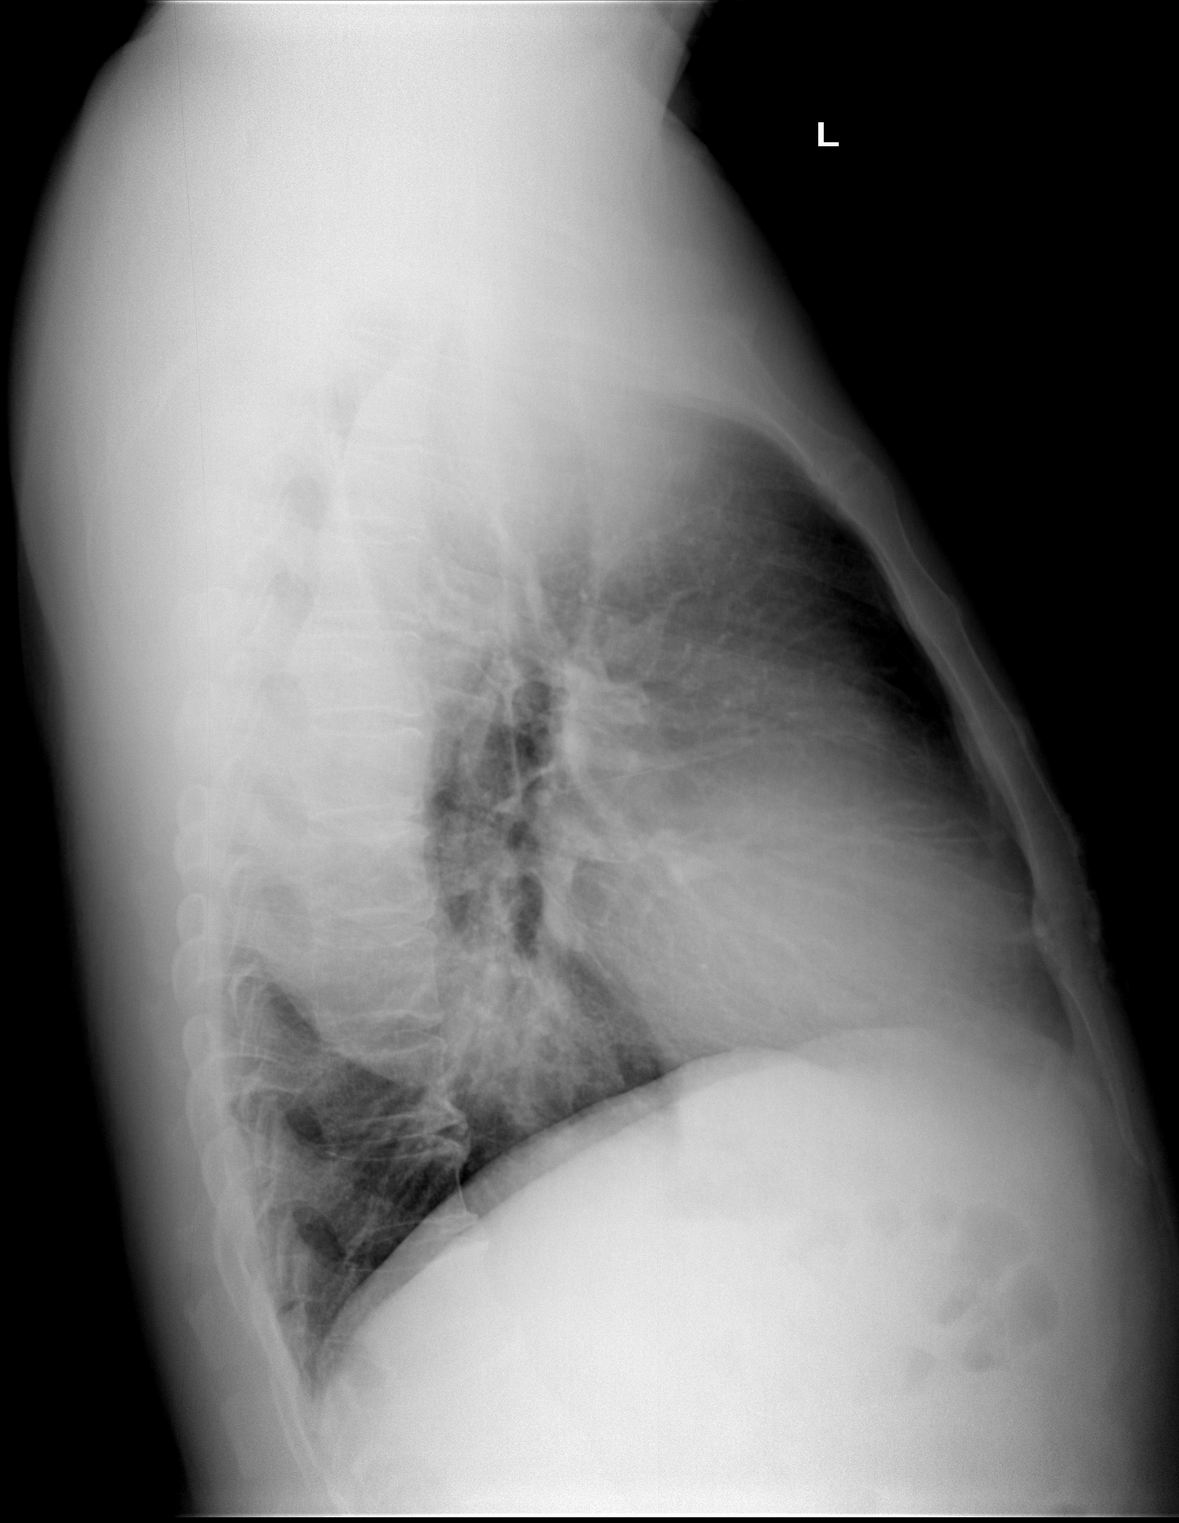

标题: x3216:间断咯血二天(结果在22楼)

间断咯血二天,bp:120/90mmmhg,心率100/分,律齐

标题: 经造影及mri 检查确诊为主动脉夹层

经造影及mri 检查确诊为主动脉夹层